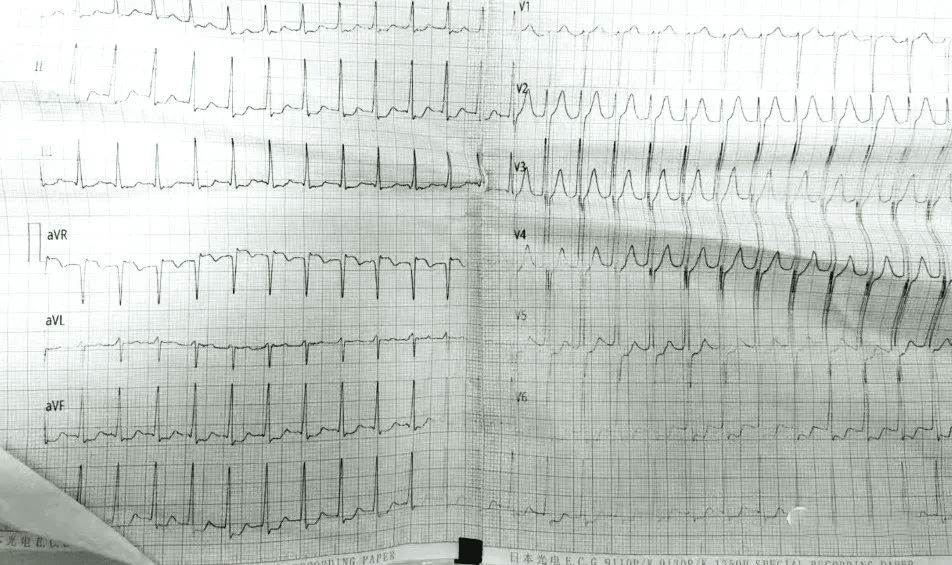

既往发作心电图,提示室上性心动过速

室上速是室上性心动过速的简称,也是比较常见的一种心律失常,发病特点是没有预兆的突然发作和停止,此时查心室率大约在每分钟150-250次,持续一段时间后又会恢复正常,但这个持续的时间是没有具体数值的,短可几分钟,长则数小时。